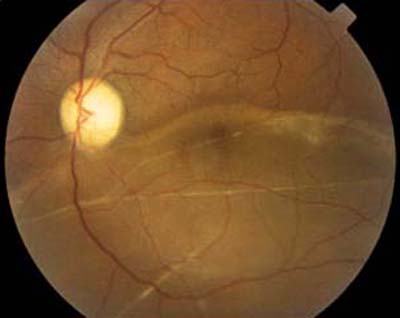

La Retinopatía Diabética es la primera causa de ceguera en U.S.A. y una de las más importantes en nuestro medio. El 25% de diabéticos tienen alguna forma de retinopatía y sólo un 10% no la presenta durante su vida.

Desprendimiento de Retina

Visión Normal

Retinopatía Diabética

Retinopatía Diabética No Proliferativa (RDNP): En un individuo sano, los vasos sanguíneos de la retina solo permiten la salida de nutrientes y oxígeno hacia la retina (no de líquido o plasma). En las personas con retinopatía diabética el contenido de los vasos (sangre y plasma) puede salir de ellos de manera anormal debido a la lesión de sus paredes por los altos niveles de glucosa. Esta acumulación de líquido en la retina dificulta su funcionamiento.

Retinopatía Diabética Proliferativa (RDP): Debido a la continua lesión que sufren los vasos sanguíneos por los elevados niveles de glucosa, muchos de ellos terminan por cerrarse completamente impidiendo la llegada de sangre y nutrientes a la zona de la retina que antes irrigaban. Estas zonas de la retina intentan obtener oxígeno y nutrientes produciendo nuevos vasos sanguíneos. Desafortunadamente estos nuevos vasos (neovasos) no tienen una función normal y crecen no sólo dentro de la retina, sino hacia el vítreo (hacia el centro del ojo, donde no debe haber vasos sanguíneos). Son estos neovasos los que pueden sangrar y producir hemorragias vítreas o pueden halar la retina para desprenderla.

Retinopatía Diabética

Visión Normal